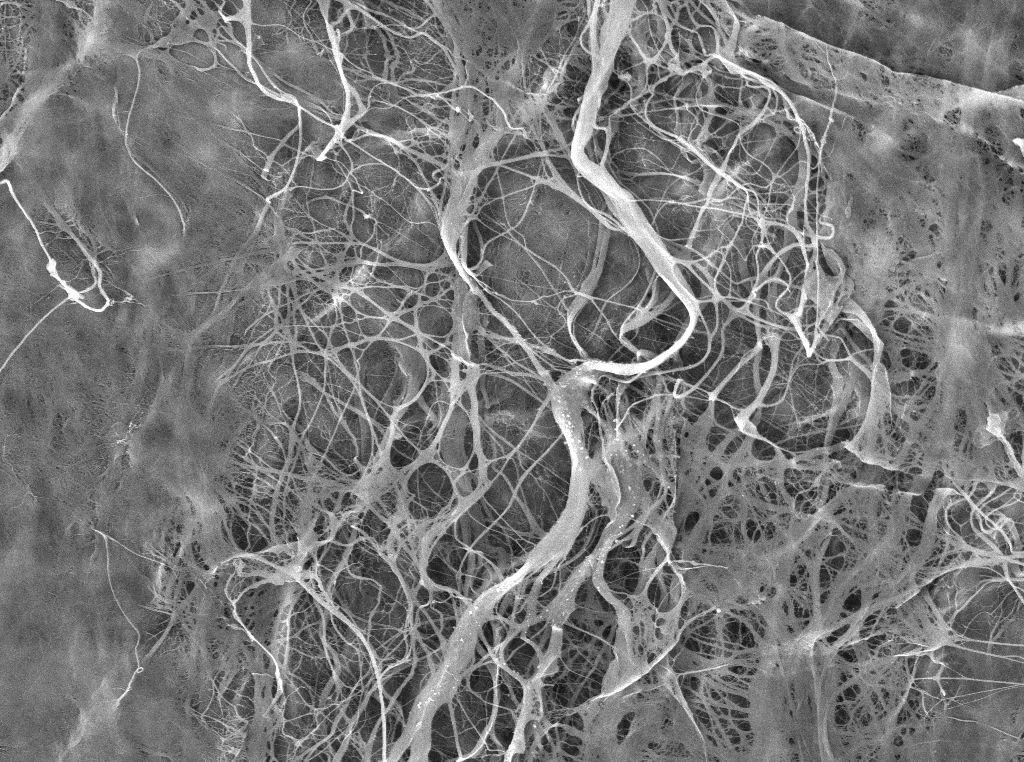

一些研究報告表明,筋膜是疼痛的重要來源,如果結(jié)締組織發(fā)生改變,筋膜組織和下層肌肉的行為可能會受到損害,從而導(dǎo)致肌筋膜疼痛。理解如何根據(jù)生理和病理參數(shù)重塑這種組織,是理解疼痛機制和制定個性化治療策略的基礎(chǔ)。

性激素受體由筋膜成纖維細(xì)胞表達(dá),隨著絕經(jīng)后婦女激素水平的降低,性激素受體的表達(dá)較低(Fede等人,2016)。此外,筋膜細(xì)胞還可以根據(jù)激素水平調(diào)節(jié)細(xì)胞外基質(zhì)成分的合成:當(dāng)β雌二醇水平低時,筋膜組織中的膠原蛋白I(從對照樣品的5.2%增加到8.4%),膠原III(從2.4%到1.5%)和彈性纖維(從0.5%到0.2%)平行減少(Fede等人, 2019)。因此,組織變得不那么有彈性,反而更堅硬,這通常發(fā)生在更年期。

相反,當(dāng)激素水平高時,通常在排卵高峰期或懷孕期間,情況正好倒置:膠原蛋白III在排卵期間上升到 6.8%,在懷孕期間上升到 6.7%,纖維蛋白-1 也是如此(從更年期的 0.2% 上升到懷孕期間的 3.6%),而膠原蛋白I下降到 1.9%(Fede 等人,2019 年)。結(jié)果是組織更柔軟、更有彈性。

這些結(jié)果突出了女性激素失調(diào)如何引起細(xì)胞外基質(zhì)合成的紊亂,改變組織的生物力學(xué)特性并引起筋膜傷害感受器的敏化。

此外,年齡似乎會影響筋膜組織重塑:事實上,結(jié)締組織在老化過程中變得更厚,有利于膠原I的增加,從而減少了它們的滑動性能(Pavan 等人,2020 年)。

在年輕(~21歲)和老年(~67歲)受試者中,對單個肌肉纖維伸長的抵抗力沒有發(fā)現(xiàn)差異。相反,細(xì)胞外基質(zhì)的貢獻(xiàn)在老年人中顯著增加(從 3.3% 增加到 8.2%);與衰老相關(guān)的被動僵硬和肌肉功能下降是由膠原纖維積累導(dǎo)致的細(xì)胞外基質(zhì)變硬引起的(Pavan 等人,2020 年)。Hansen等人證明,與雌激素水平的降低一起,這種機制可以與IGF-1(胰島素生長因子1)的上調(diào)有關(guān),IGF-1增強了膠原蛋白的合成。